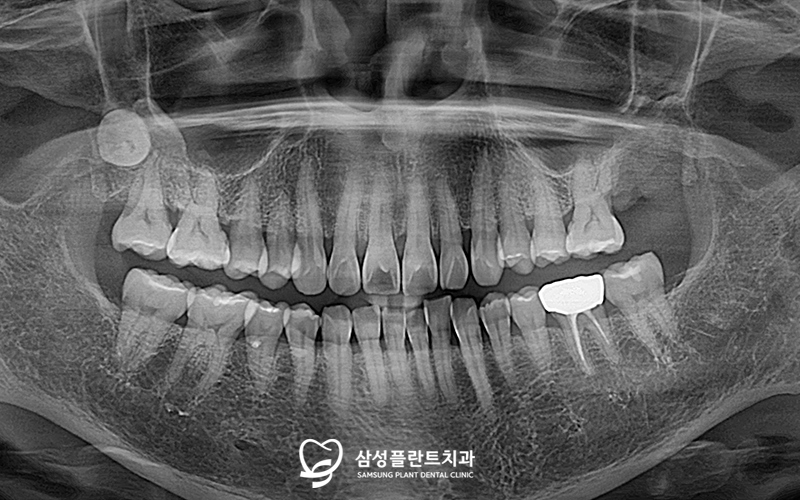

파노라마 사진을 촬영해 체크해보니

불편을 호소하는

노란색 표시의 어금니는

잇몸뼈가 녹고 염증소견도 관찰되었습니다.

또한 매복된 사랑니(주황색 표시)도

확인할 수 있었답니다.